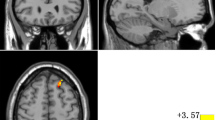

Compared to HCs, patients with OCD exhibited lower spFC and lpFC in the left precentral/postcentral gyrus (t = -5.57 and -5.43; P < 0.05, GRF corrected), and higher lpFC in the right thalamus/caudate, left thalamus, left inferior parietal lobule (IPL), and left cerebellum Crus I/VI (t = 4.59, 4.61, 4.41, and 5.93; P < 0.05, GRF corrected) (Table 2, Fig. 3, and Fig. 4). The VBM results showed no significant differences in the GMV values of the left precentral/postcentral gyrus, right thalamus/caudate, left thalamus, left IPL, and left cerebellum Crus I/VI between the two groups (TableS1 in the Supplementary Materials).

Brain regions with significant differences in lpFC between patients with OCD and HCs. Red and blue denote higher and lower FC in patients. The color bar represents the T values from two-sample t tests. L = left; R = right; lpFC = long-range positive functional connectivity; OCD = obsessive–compulsive disorder; HCs = healthy controls